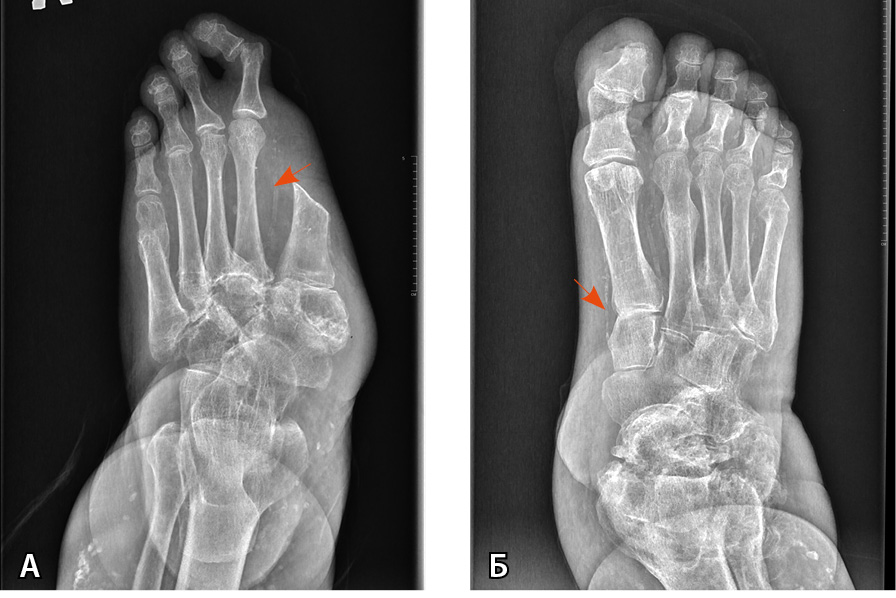

В 2003 г. травма правого голеностопного сустава, диагностирован лодыжечный перелом, обусловленный ДНОАП, наложена индивидуальная иммобилизирующая повязка Total Contact Cast, которую пациент носил в течение 6 месяцев. В 2009 г. травма левой стопы с формированием нейропатической язвы, диагностирована подострая стадия ДНОАП. В 2017 г. парциальная резекция пролабирующей кубовидной кости слева. В 2020 г. ампутация I пальца левой стопы с резекцией головки I плюсневой кости по поводу остеомиелита (рис. 2, 3).

Рис. 3. Рентгенограмма обеих стоп пациента Т. в прямой проекции (стрелками указаны кальцинированные сосуды):

А – артропатическая перестройка структуры костей предплюсны, переломы на уровне оснований 3–5-й плюсневых костей с признаками консолидации. Консолидированный перелом головки 5-й плюсневой кости. Ампутация I пальца;

Б – артропатическая перестройка структуры костей предплюсны и правого голеностопного сустава, консолидированные переломы II, III, V пальцев. Остеомиелит ногтевой фаланги I пальца

Несмотря на выявление хронического остеомиелита дистальной фаланги I пальца правой стопы, обусловленного рецидивирующими нейропатическими язвенными дефектами в анамнезе, антибактериальная терапия нашему пациенту в настоящее время не показана в связи с ремиссией воспалительного процесса и отсутствием трофических поражений стоп. Пациент продолжает носить индивидуальную сложную ортопедическую обувь.